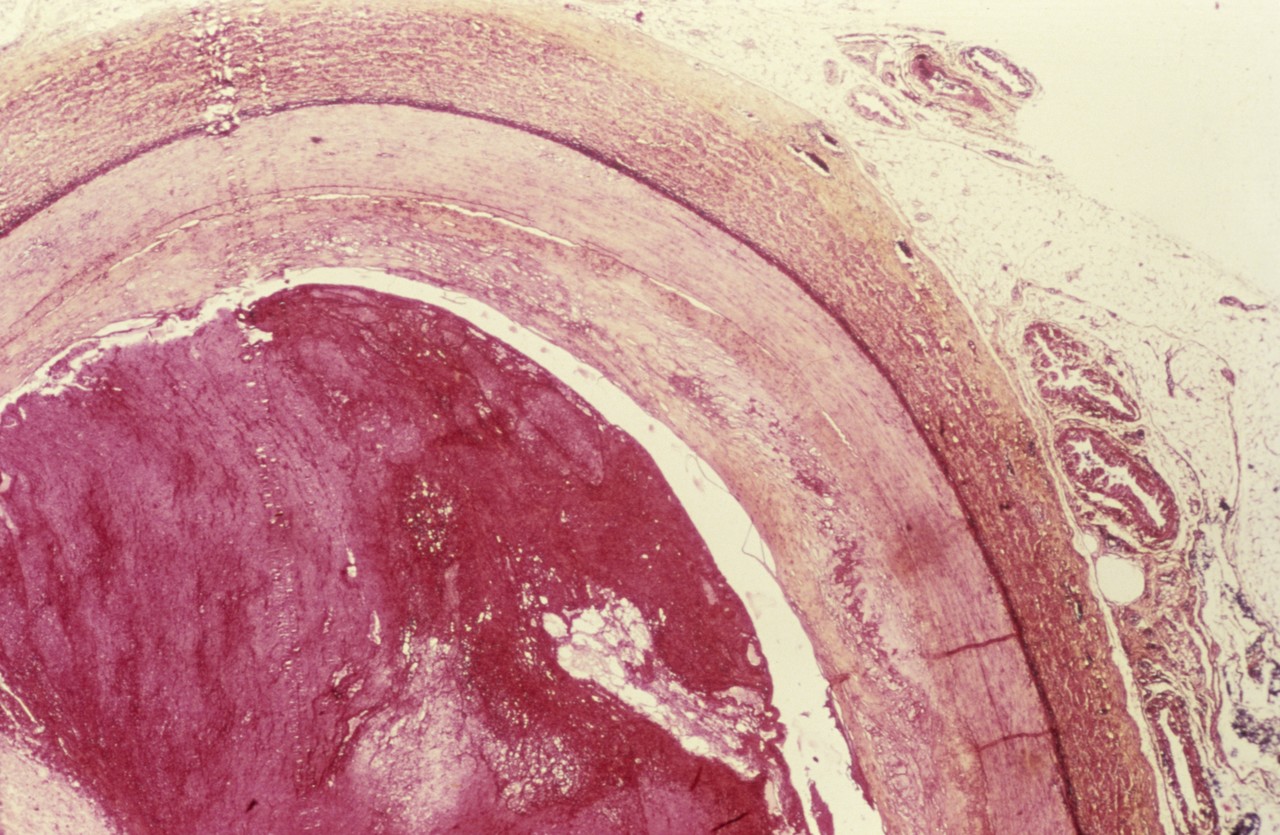

유전성 아밀로이드증(Hereditary Amyloidosis)은 현재까지 국내에서 알려진 환자 수가 100명이 되지 않는다. 트랜스티레틴 아밀로이드 심근병증(Transthyretin Amyloid Cardiomyopathy)이라 불리는 ATTR-CM은 혈액 내에서 자연적으 로 순환하는 운반 단백질인 트랜스티레틴(TTR)이 불안정해지며 심장이나 다른 인체 장기에 쌓이는 치명적인 희귀질환이다.

유전적 돌연변이나 노화로 인해 혈액 내에서 자연적으로 순환하는 운반 단백질인 트렌스티레틴이 불안정해지게 되고, 비정상적인 단백질은 뭉쳐서 아밀로이드를 형성한다. 생성된 아밀로이드는 혈류를 통해 이동하며 신체 기관에 쌓이는데, 심장에 쌓일 경우 심근이나 심장벽이 두꺼워지고 경직되며, 궁극적으로 심부전을 유발하게 된다.